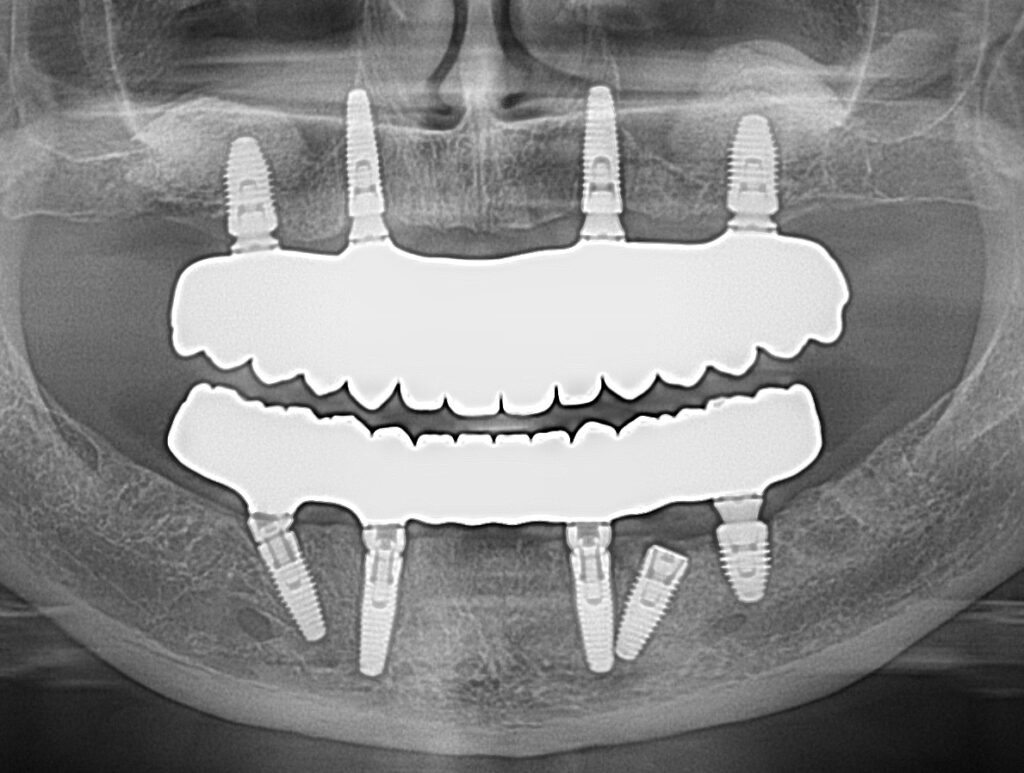

A selection of full arch fixed implant bridge patients after 5 years of wear